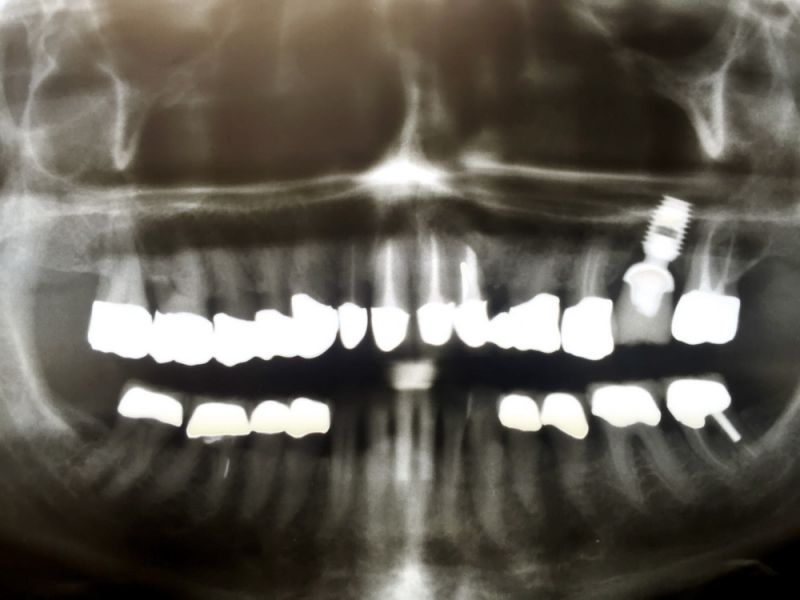

Patientin gestern im vierteljährlichen Recall

Bei dieser Patientin befinden sich die vor 20 Jahren erstellten Kronenversorgungen, bis auf eine neu erstellte Krone auf einem Implantat, nach wie vor im Mund.

Die Patientin mit allerschwersten chronischen Schmerzzuständeen ist seit 20 Jahren vollkommen schmerz- und beschwerdefrei.